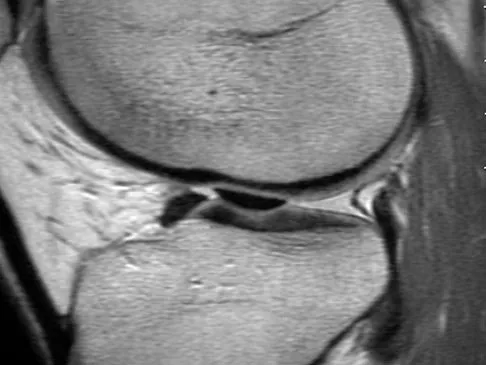

A 37-year-old man with a history of congenital flatfoot reports worsening pain on the medial aspect of his ankle for the past year. The pain is worse with weight bearing and is better with rest and the use of an ankle brace. What findings are shown on the MRI scans shown in Figures 18a through 18c?

Explanation